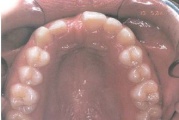

Koonilise kujuga lisahammas ülemiste tsentraalsete lõikehammaste vahel.

Suulaepoolt lõikunud koonilise kujuga lisahammas